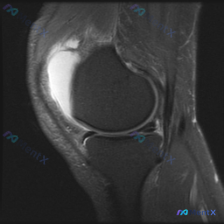

本次仅提供单张膝关节矢状位T2加权MRI图像,用户关注核心问题为「半月板异常」,无其他临床病史、体征信息。

- 髌上囊区可见明显均匀T2高信号,提示大量膝关节积液,这是图像最突出的异常;

- 半月板形态基本完整,未见高信号穿透关节面的III级撕裂信号;

- 髌腱走行、信号正常,交叉韧带可见范围内无明确中断、增粗或水肿;

- 未见明确的半月板III级撕裂;

- 受限于单张图像和分辨率,无法完全排除I/II级退变或微小损伤,需要结合其他序列评估;

- 本次最突出的发现是关节积液,而非半月板显著结构异常,积液可能是膝关节其他病变的继发反应。

这张单幅MRI最突出的异常是髌上囊大量单纯关节积液,无明确严重半月板撕裂或其他结构性破坏;病因方向优先考虑炎症/代谢性因素,也就是结晶性关节炎、非特异性滑膜炎,必须警惕排除感染性病因,而非半月板机械性损伤。